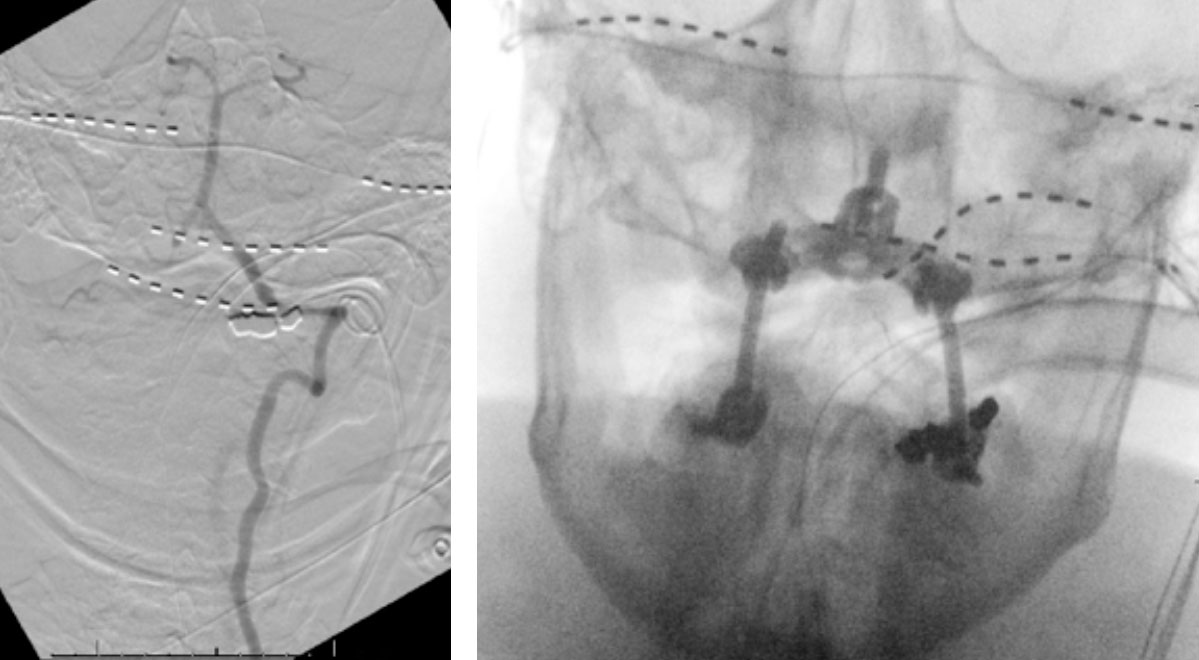

During neutral positioning, the vertebrobasilar circulation fills briskly from the Right Vertebral Artery. (Figure 4)

On rotation to the left, the patient experienced mild symptoms, however no significant Vertebral Artery or basilar reduction in flow was observed. On rotation to the right, the patient experiences slightly more moderate symptoms, however no significant Vertebral Artery or vascular reduction flow was observed. On hyper extension of approximately 10-15 degrees, passively performed by the patient until symptoms are reproduced, angiogram demonstrates complete occlusion of the right Vertebral Artery at approximately the C2-C1 level. (Figure 5)

It is unclear whether there is a specific bony osteophyte or soft tissue mass that is resulting in the compression. Live fluoroscopy within the neutral and extension position does demonstrate extensive arthritis and hypertrophic changes within the C1/C2 region, however specific anatomic compression is difficult to determine.